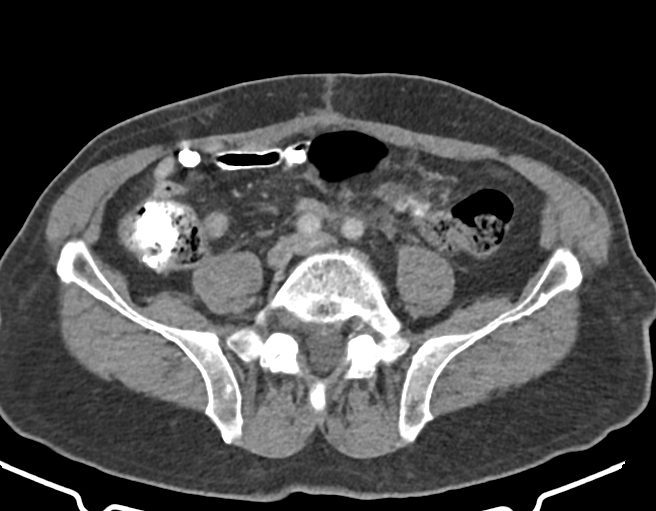

در سي تي اسکن اسپيرال شکم و لگن با و بدون کنتراست- تري فازيک کبد (مولتي ديدکتور 16 با مقاطع ظريف و بازسازي هاي ساژيتال و کرونال):

– سوچورهاي اوپک در محل اناستموز رکتو سيگموئيد، بدون نشانه هاي عود لوکال

– توده هيپودنس به قطر 35 mm در قسمت تحتاني سگمان 6 کبد (بدون تغيير نسبت به سي تي اسکن 1399/07)

– نشانه هاي التهاب در چربي مزانتر مجاور محل اتصال کولون نزولي به سيگموئيد و تصوير شبيه به توده به ابعاد mm 23 x 38 در کنار آن (که نسبت به سي تي اسکن قبل جديد مي باشد)

– کيست کورتيکال 22 mm در قسمت مياني کليه چپ

– سنگ 13 mm در مثانه

– اسکار جراحي در خط وسط ديواره شکم در سوپرا پوبيک

– کلسيفيکاسيون ديواره ائورت و شريان هاي ايلياک

– چربي در کانال اينگوينال راست مطرح کننده هرني